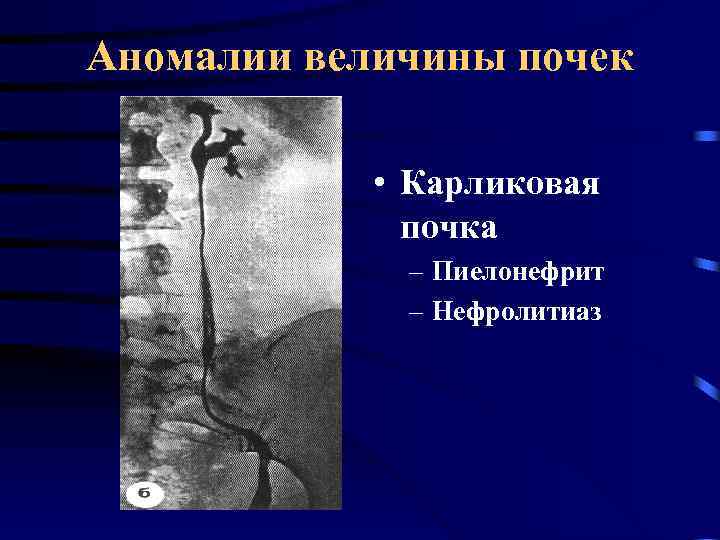

Аномалии величины почек • Карликовая почка – Пиелонефрит – Нефролитиаз

Аномалии величины почек • Карликовая почка – Пиелонефрит – Нефролитиаз